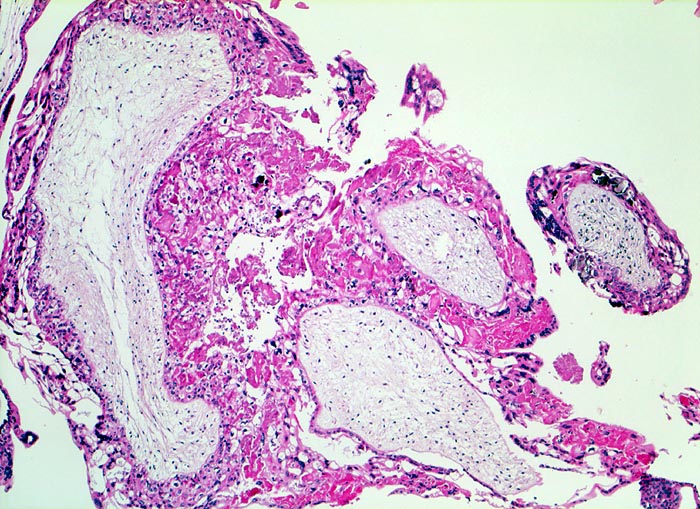

Makroskopisch ist die Plazenta deutlich grösser als erwartet für das Schwangerschaftsalter. Sie ist diffus von bis 2cm grossen Zottenblasen durchsetzt, welche nach Kollaps jedoch der makroskopischen Entdeckung entgehen können. Beim Aufschwemmen in Flüssigkeit entfalten sich die Blasen wieder. Mikroskopisch sind die Zotten aufgrund einer grobblasigen pseudozystischen Hohlraumbildung im Zottenstroma überwiegend grosskalibrig. Im Zottenstroma sind nur ganz vereinzelt Kapillaren nachweisbar. Im Gegensatz zu hydropisch geschwollenen Zotten im Sinne eines Regressionsphänomens zeigen die Zotten bei Blasenmole zusätzlich eine zirkumferentielle Hyperplasie von Synzytio- und Zytotrophoblast mit fakultativer Zellatypie. Bei herdförmiger Mole (> 3725) sind diese Veränderungen nur in einem Teil der Plazentarzotten ausgeprägt.

• Stark vergrösserte und verplumpte Plazentarzotten.

• Hydropisch umgewandeltes Zottenstroma ohne Gefässe mit Ausbildung von pseudozystischen Hohlräumen (Blasen)

• Trophoblastinklusionen und Kerntrümmer im Zottenstroma.

• Deziduafragmente

• Blutkoagel